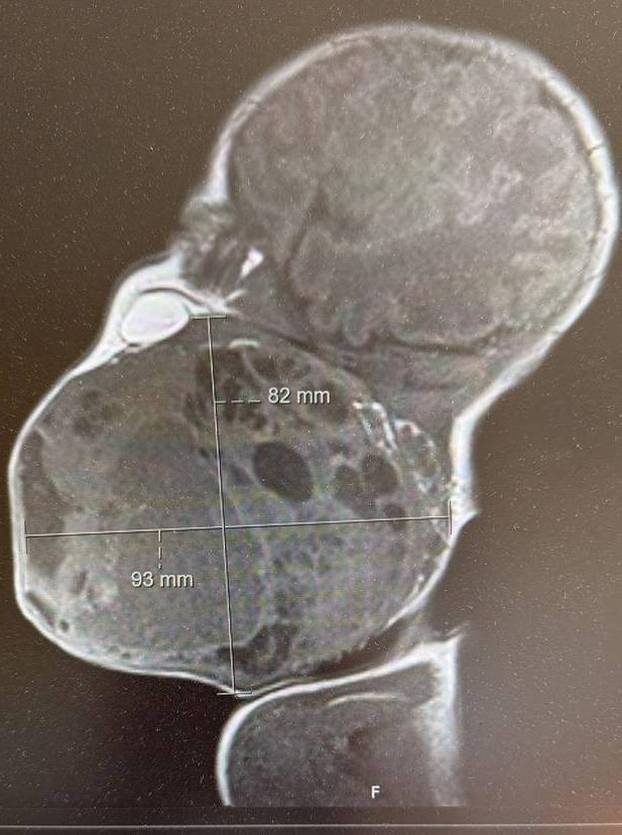

Liječnici KBC-a Zagreb izveli su nevjerojatan zahvat prvi put - operirali su novorođenče dok je još bilo djelomično u maternici majke, spojeno na posteljicu i pupkovinu, kako bi mu spasili život. Tijekom carskog reza liječnici su izvadili samo glavu, vrat i dio prsnoga koša bebe, a ostatak tijela ostao je u maternici kako bi dijete i dalje primalo kisik putem posteljice. Tako je tim dobio dragocjeno vrijeme za osiguravanje dišnog puta jer je beba na vratu imala golem tumor, veličine vlastite glavice, koji je potpuno zatvarao dišne putove.

- Nisam znala da takve dijagnoze uopće postoje u trudnoći. Brzo sam se sabrala i sve predala u Božje ruke. Na kraju je sve ispalo dobro, s minimalnim posljedicama. Nakon prvotnog šoka, nekako sam trudnoću provela u miru, nisam htjela da beba osjeti moju zabrinutost. Trudila sam se da se ne opterećujem mogućim negativnim ishodima. Nakon što je otkriven tumor, napravljen mi je magnet i tumor je potvrđen. Pitali su me želim li prekinuti trudnoću, a ja sam rekla da ne želim. Sazvan je konzilij, i dogovoreno je da će me redovito pratiti ultrazvukom iz tjedna u tjedan kako bi se vidjelo hoće li biti dodatnih komplikacija za srce i bubrege. Komplikacija, srećom, nije bilo. Tumor je rastao zajedno s bebom. Na početku su rekli da će, ako sve prođe bez komplikacija, napraviti ovu specifičnu vrstu poroda i tako je na kraju i bilo. Rodila sam na Rebru, u općoj anesteziji - ispričala je za 24sata mama Anita.

Prof. prim. dr. sc. Vesna Elveđi Gašparović, voditeljica odjela babinjača, kazala je kako je fetus imao velik tumor na vratu veličine kao glavica.

Prema riječima doc. dr. sc. Davida Ozretića, tumor je već u trudnoći bio iznimno velik i prijetio je potpunim zatvaranjem dišnog puta.